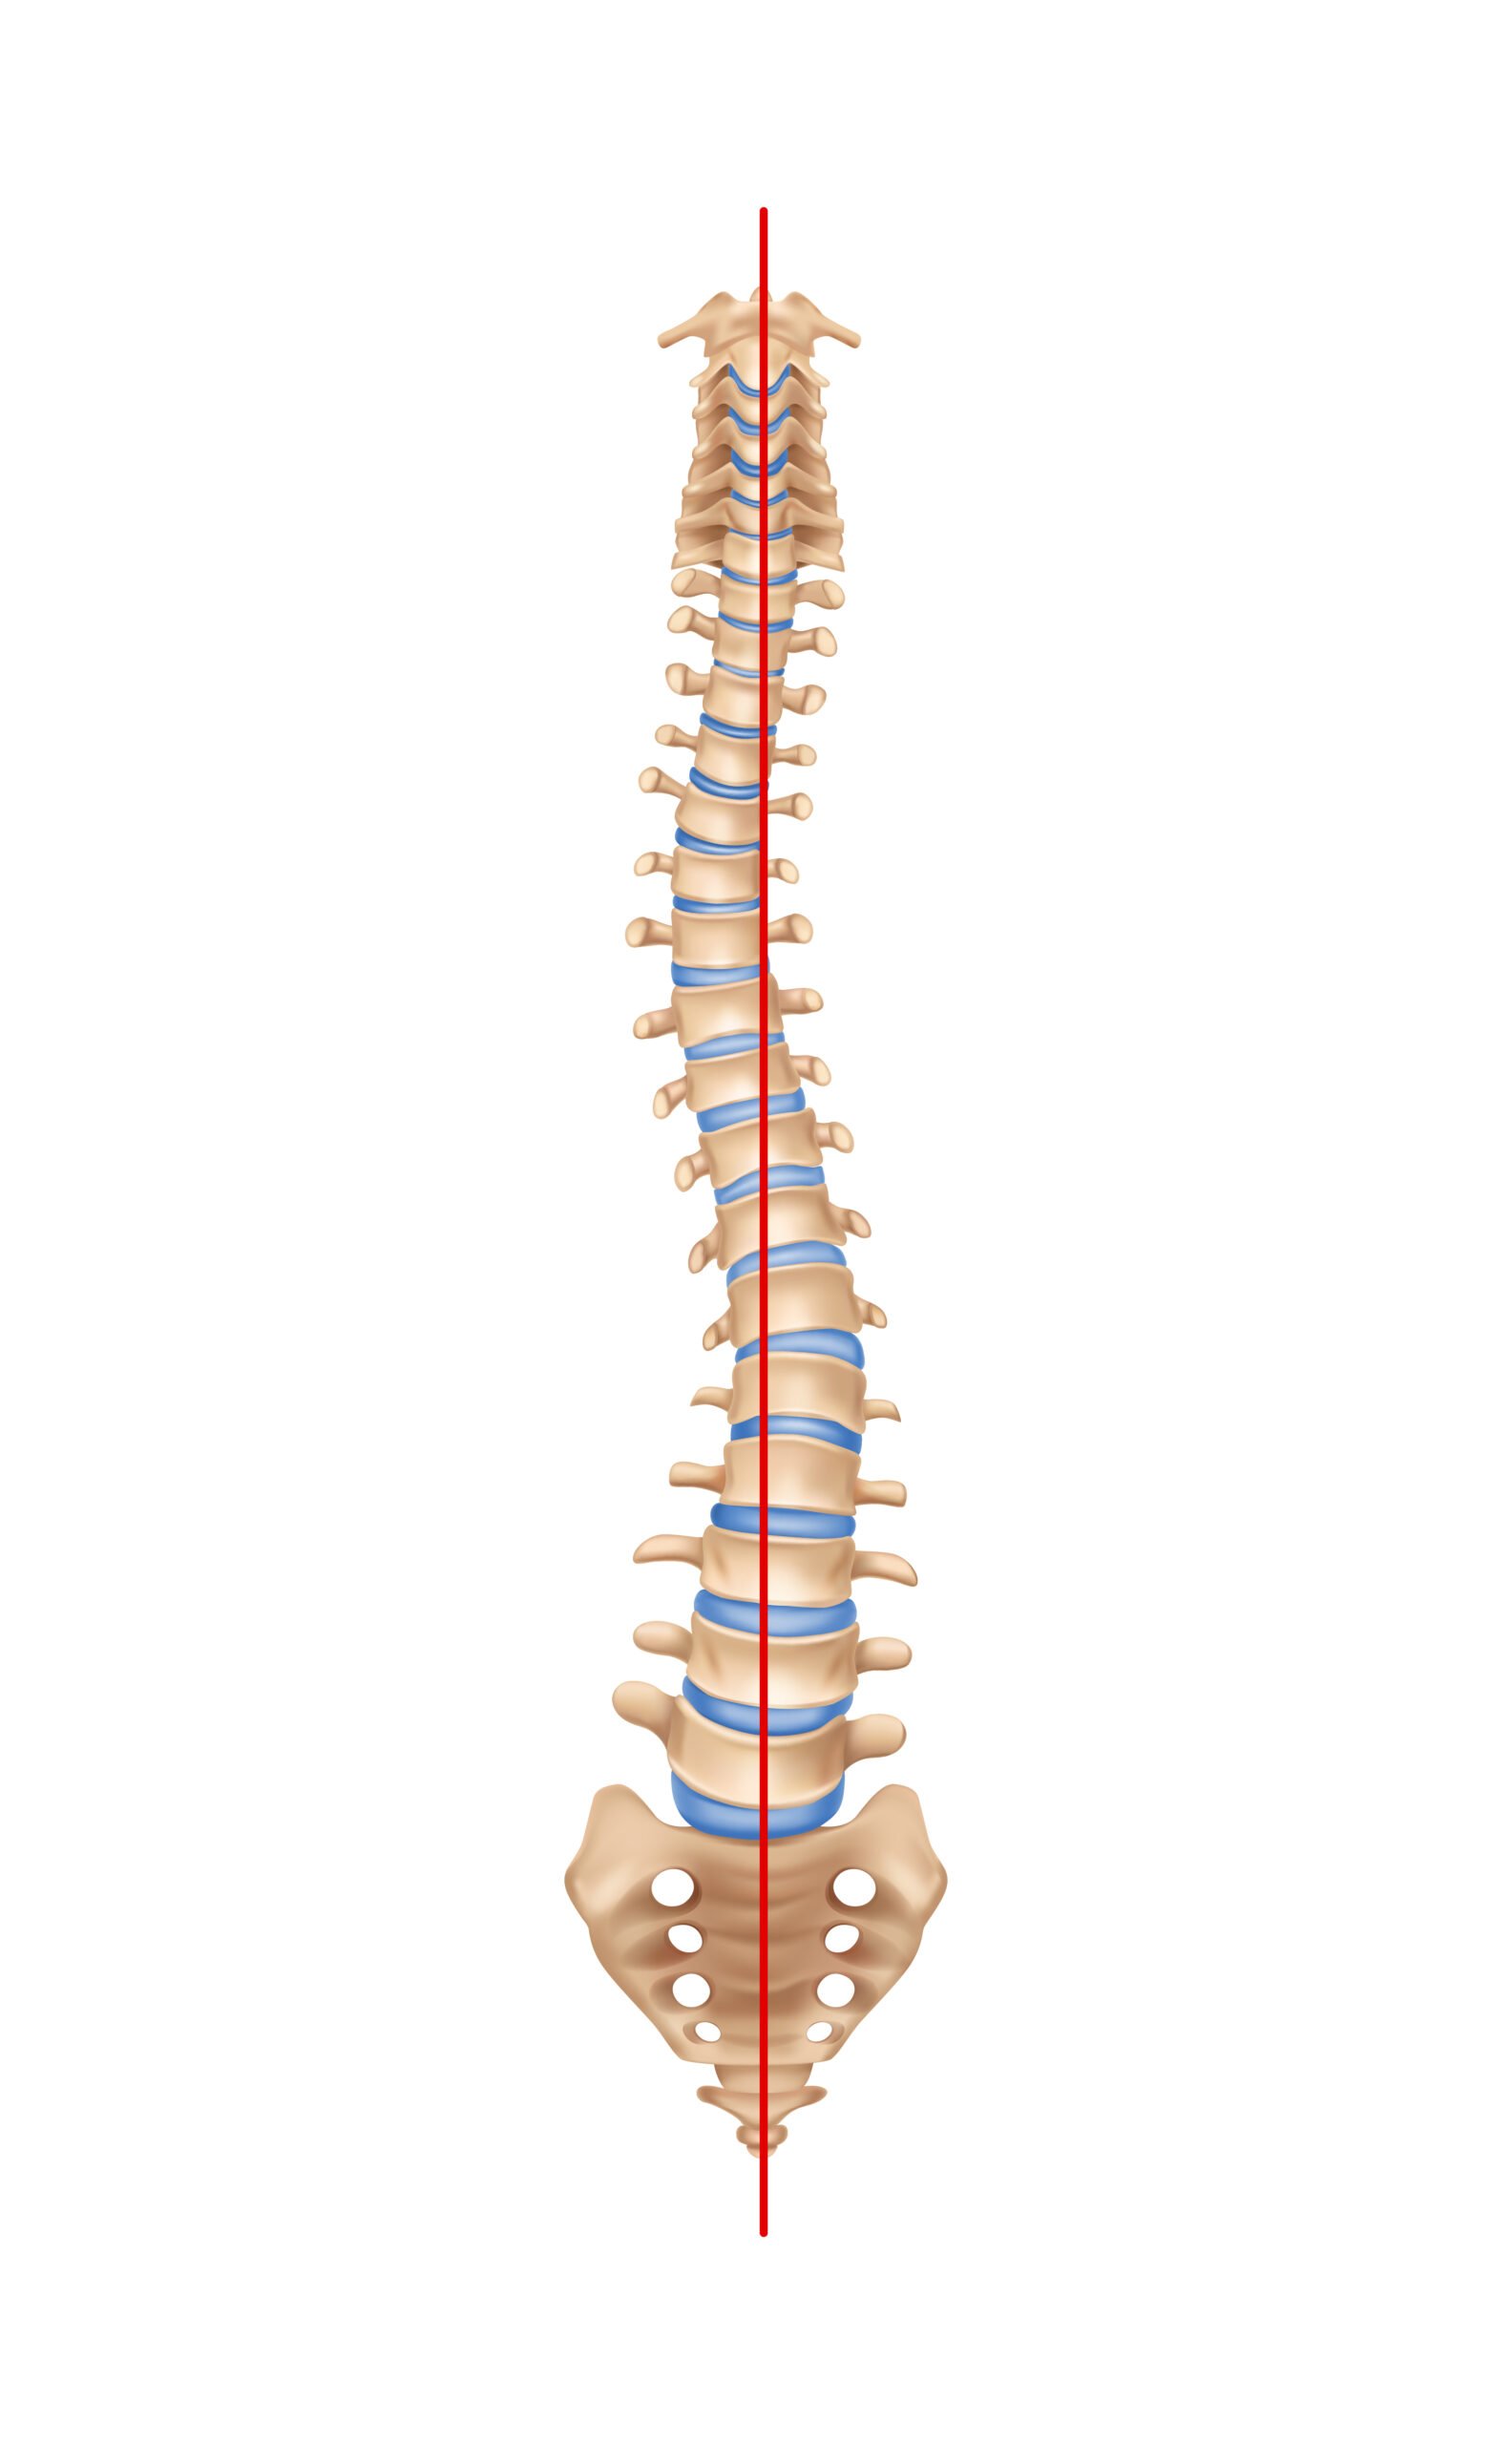

Orthopaedic physiotherapy is concerned with the treatment of disorders or injuries of the skeletal system and associated muscles, joints and ligaments.

Orthopaedic conditions treated by physiotherapist include:

Spondylosis

Ankylosing Spondylitis

Spinal Deformities

Spondylolisthesis